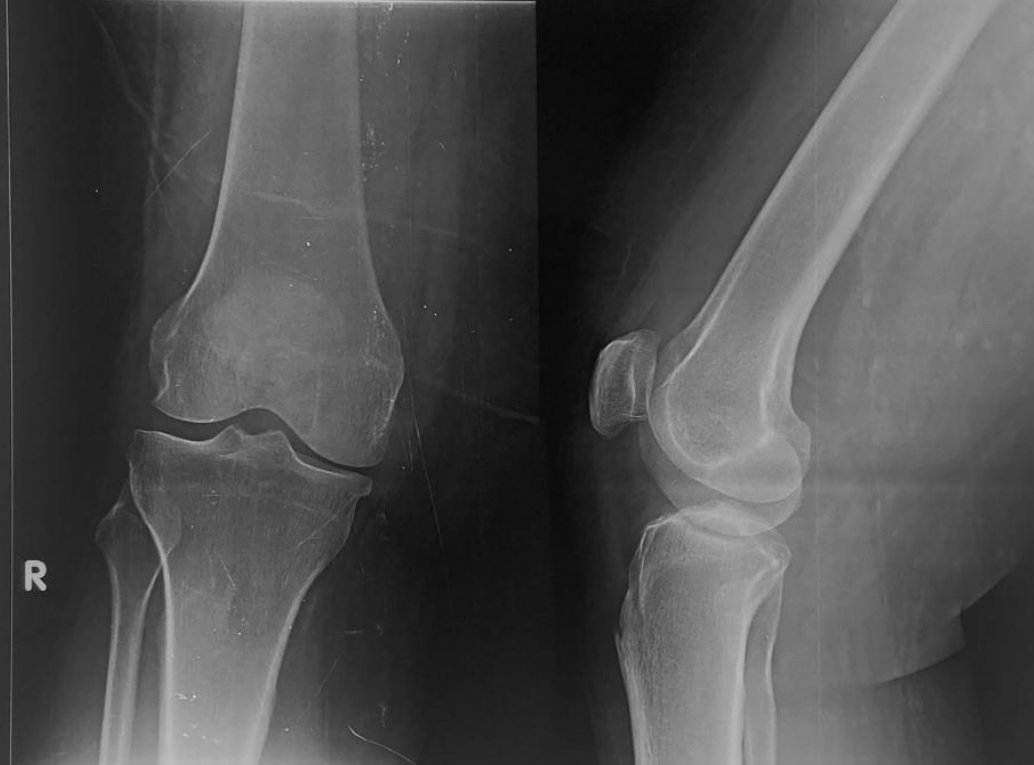

Before Surgery

Before